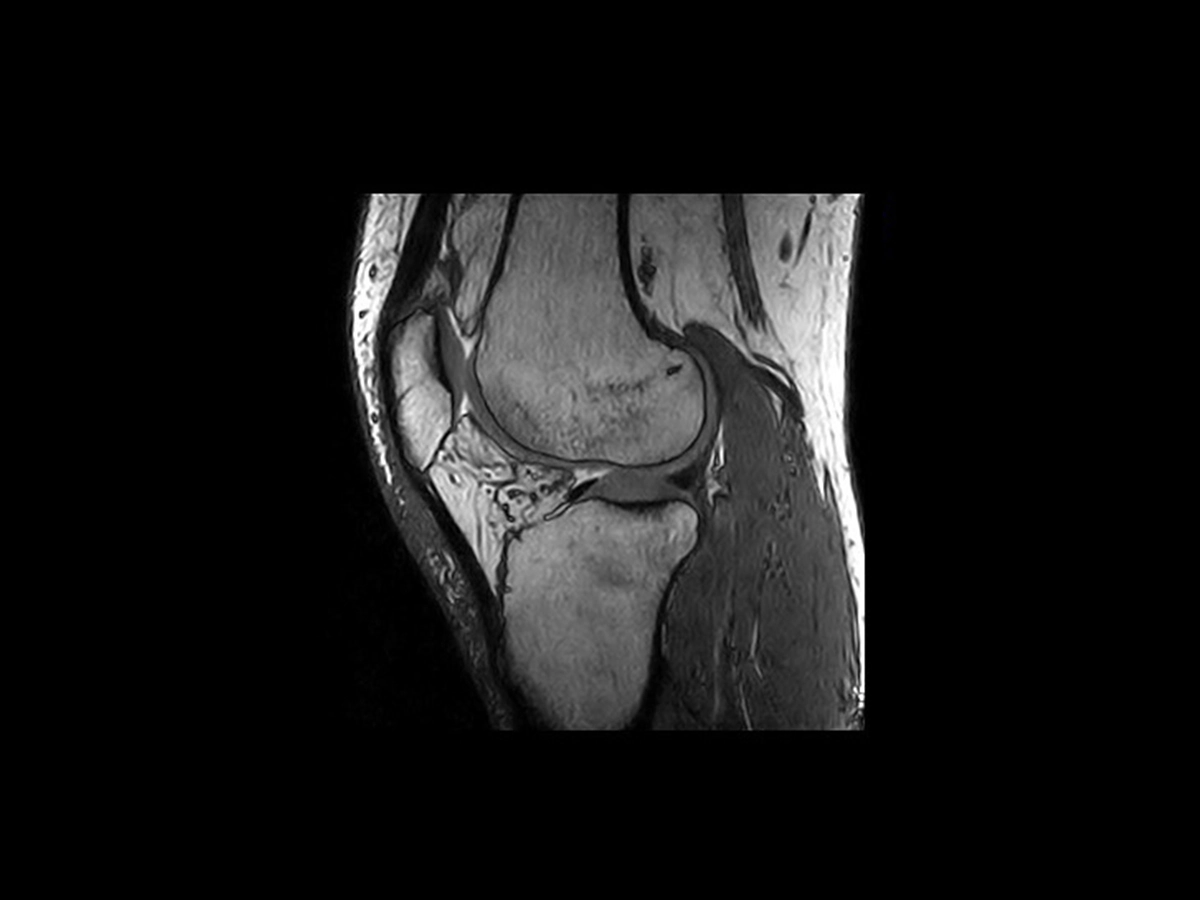

The demand for accurate and rapid diagnosis of the injuries of professional athletes and the increasing number of people participating in sports has prompted the adoption of different medical imaging modalities. Indeed, Sports Medicine MRI stands out for its effectiveness, especially in detailing soft-tissue injuries, and plays a crucial role in assessing muscle damage and intra-articular lesions such as meniscal and cartilage injuries. Its widespread use guides orthopedic surgeries, particularly for muscle, tendon, joint injuries, and stress fractures, enhancing overall outcomes.

Thanks to True-Motion, which promotes optimal patient care due to the open configuration, MRI guides orthopedic surgeries by providing a detailed roadmap for surgeons allowing detailed analysis of motion-related pathologies. The low field ensures optimal imaging even in the presence of metal implants, as well as a maximized safe patient experience.

True-Motion offers significant benefits in imaging pathologies linked to position or movement. It could be seamlessly integrated into regular MRI sequences with minimal additional time compared to standard exams. This tool adds value to exams by enabling real-time visualization of joint movement and it could be particularly advantageous for post-operative evaluations.

The ability to observe joint motion becomes differentiating for certain pathologies because it allows you to see aspects that would otherwise be invisible. In sports medicine, True-Motion is therefore a specialized tool that meets the specific diagnostic needs of athletes, ensuring uncompromised accuracy in the diagnosis. This innovation represents a valuable resource, as it improves the scope and precision of medical imaging, especially in scenarios where movement plays a fundamental role in the evaluation of pathology.